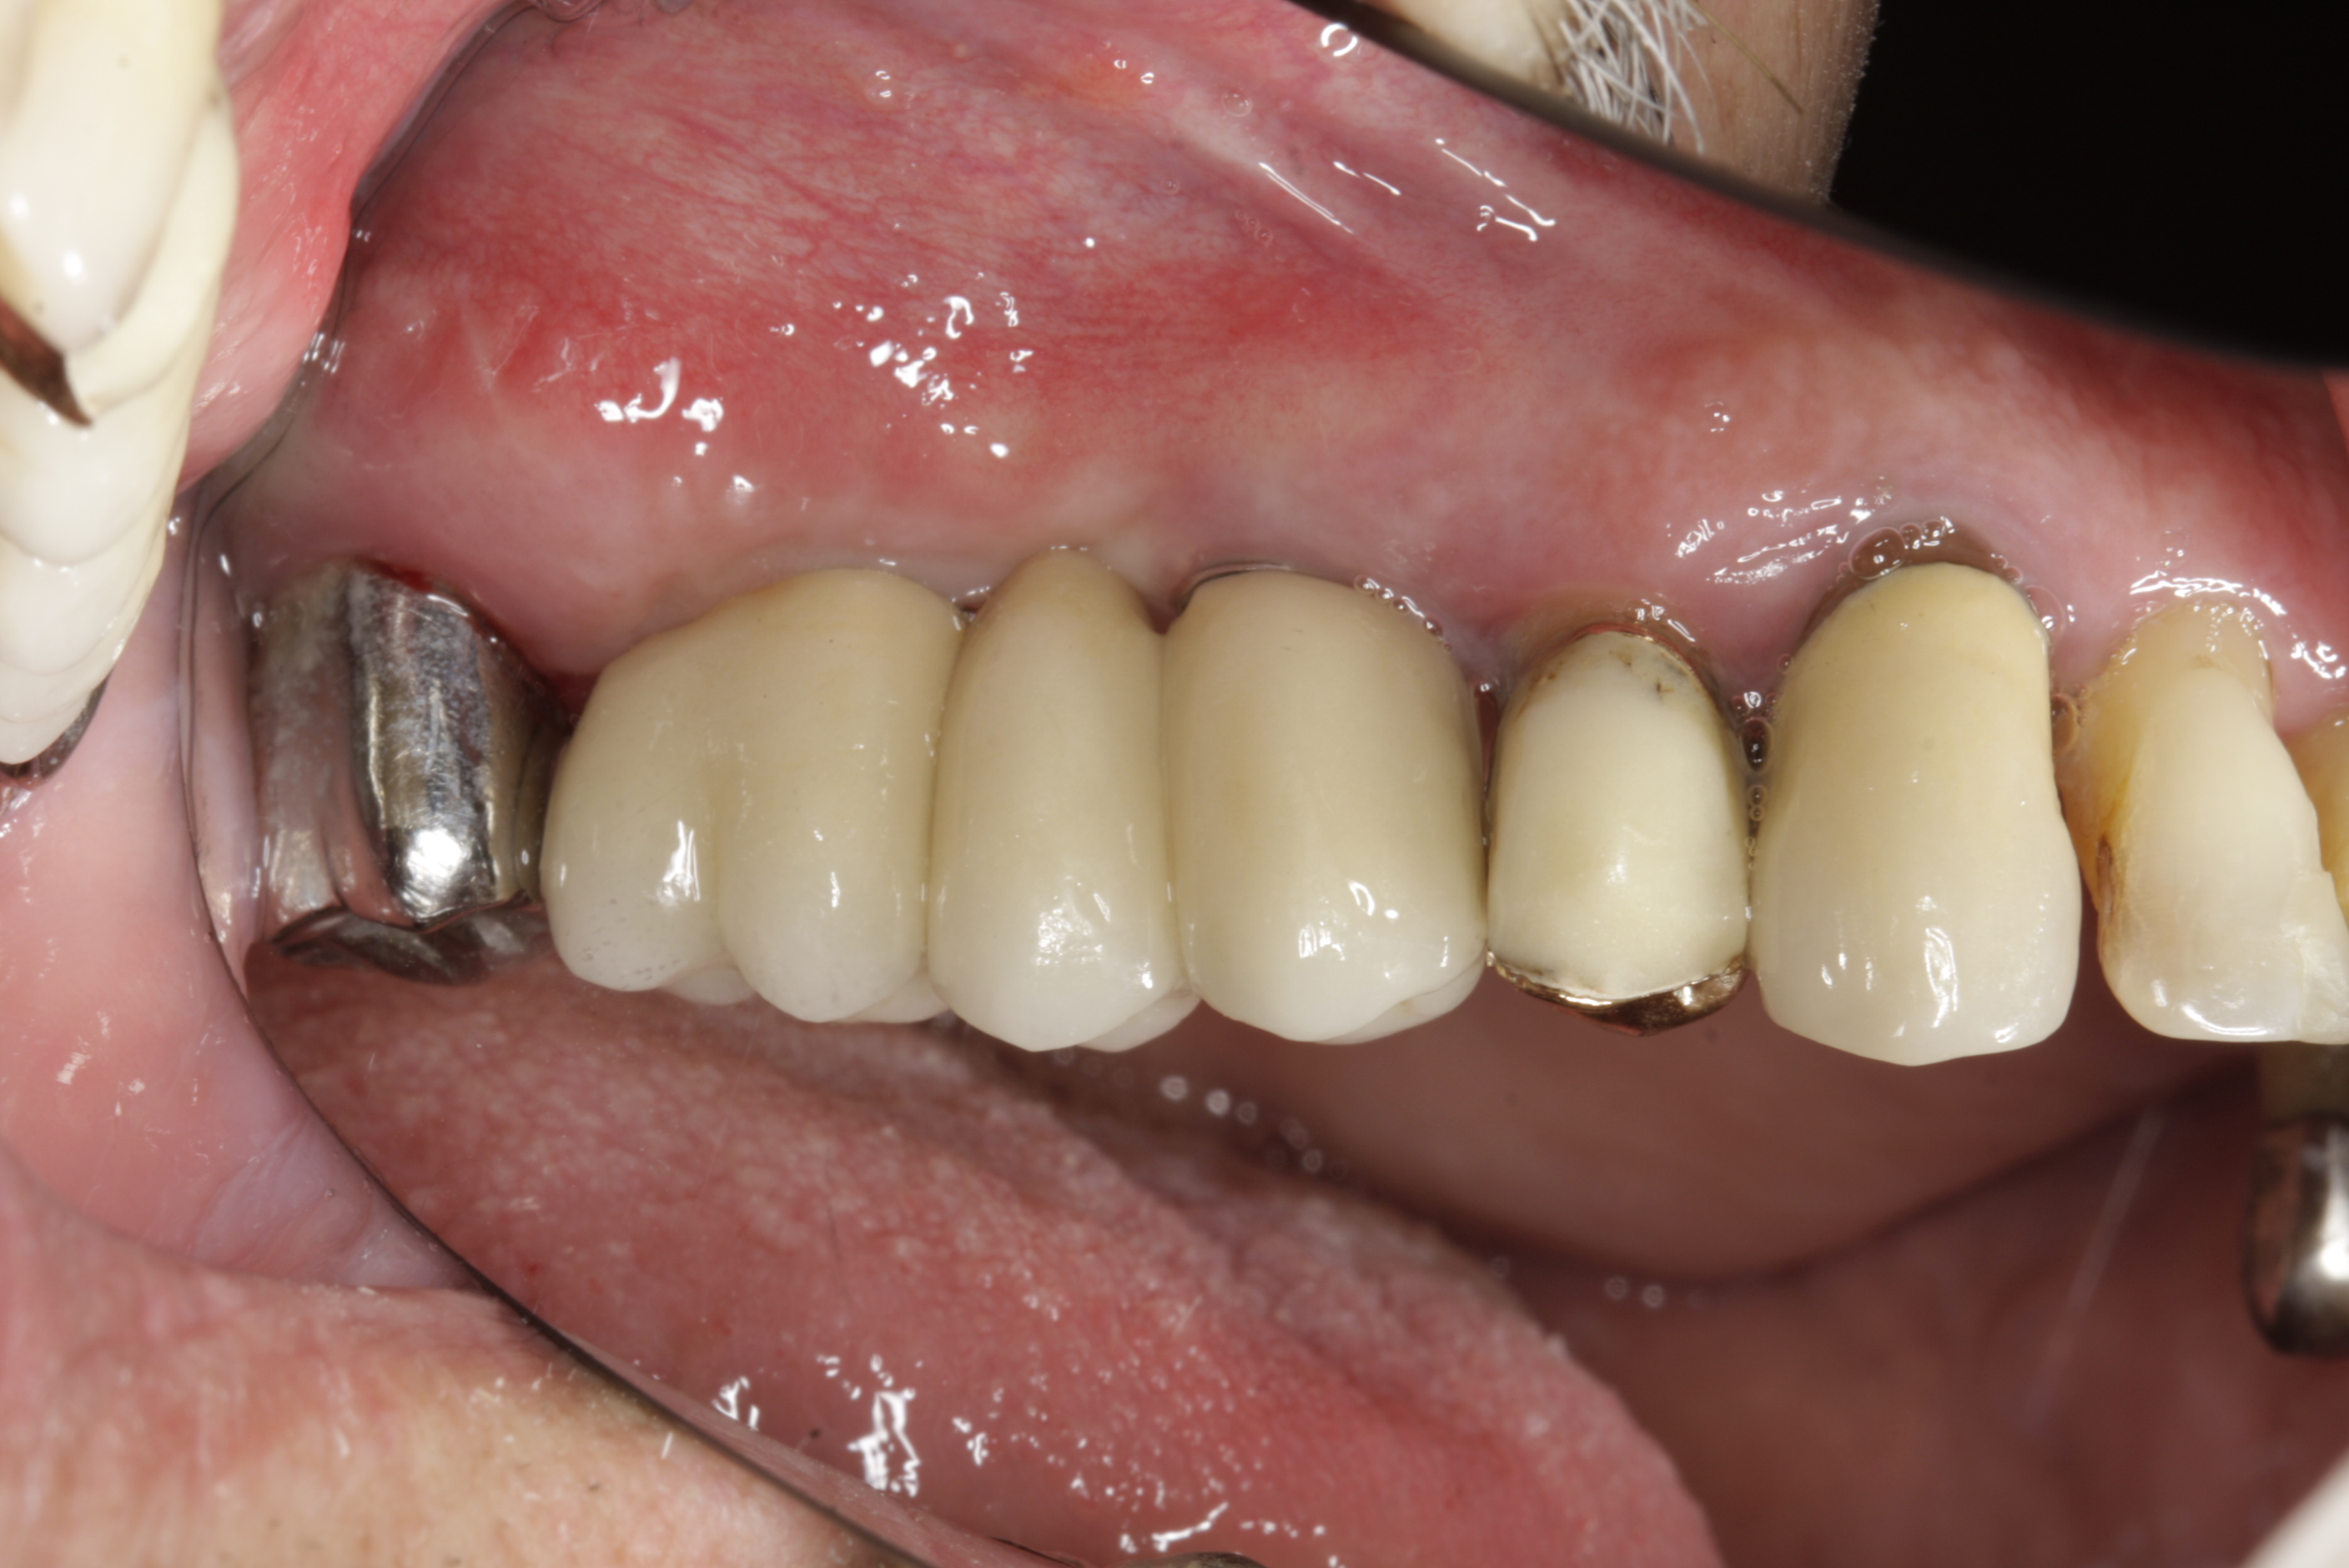

Velká mezera

V případě chybění většího počtu zubů v postranních úsecích čelistí je možné ošetření pomocí implantátů, které nahradí ošetření pomocí snímacích náhrad kotvených na zbývajících zubech nebo patře.

Podmínkou je opět dostatečné množství kosti.

Protetické řešení může být pomocí můstku, který je kotvený na implantátech nebo pomocí jednotlivých korunek na implantátech.

V zásadě je možné do těchto můstků zařadit i přirozené zuby, zejména pokud je potřeba tyto zuby ošetřit proteticky – korunkami. Korunky nebo můstky mohou být na implantáty nacementovány nebo přišroubovány.

Zdravé zuby zůstanou zachovány a přitom náhrady jsou pevné, jako na vlastních zubech